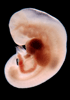

Carnegie Stage 14 (32 post-ovulatory days)

Most embryos at stage 14 are approximately 32 postovulatory days old and measure 5-7 mm in length. Distinguishing criteria for this stage include an open lens pit with invagination of the lens disc and elongated and tapering upper limb buds. The otic vesicle with a well-defined endolymphatic appendage is also a hallmark of this stage.